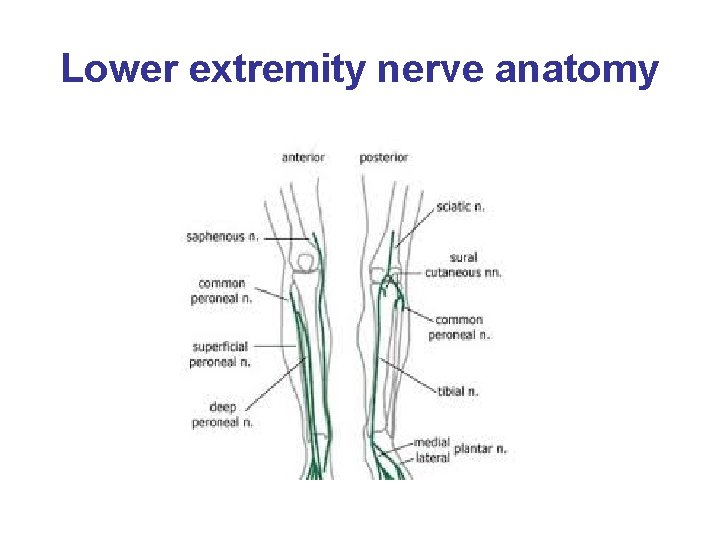

Lower extremity nerve anatomy